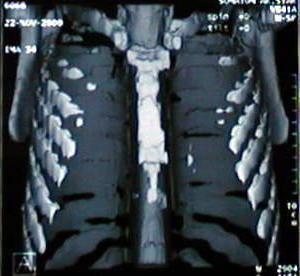

Reconstrucción Osea Tomográfica

• El esternón frente y lateral:

• observe la convexidad del cuerpo esternal y la concavidad que ocasiona el desplazamiento anterior del pronunciado apéndice sifoides.

• Las estructuras mediastinales se alojan en un tórax que ha disminuido su diámetro antero-posterior por la depresión esternal y la marcada concavidad de la columna dorsal.

• La reconstrucción ósea torácica tomográfica demuestra que las alteraciones presentes en el tórax están limitadas básicamente al defecto esternal.

• Los arcos cartilaginosos costales, causantes de los defectos del tórax están ausentes, en el proceso de reconstrucción tomográfica.

•  Procedimiento de estudio computarizado, mediante el cual las imágenes tomográficas son superpuestas con ayuda de un software especial y permite una proyección tridimensional de los elementos óseos, dando una imagen aspecto 3D, de volumen y distribución con alto contenido docente y demostrativo. el aporte de esta tecnica en esta patologia es unicamente con fines conceptuales demostrativos docentes.